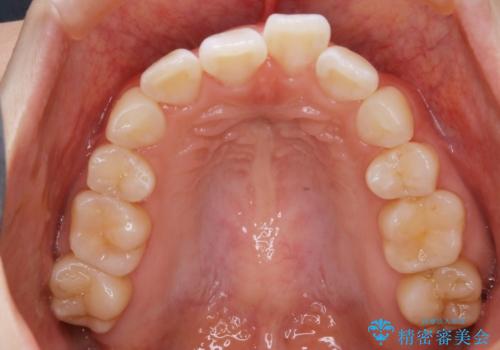

- 以前、中学生から高校生にかけてワイヤー装置による抜歯矯正を経験されている患者さんで、大人になってからのライフスタイルの変化でリテーナーを継続使用することができず、ガタつきが目立つようになってきてしまったのでもう一度矯正治療がしたいという主訴でご来院されました。

既に上下左右の4番目の歯が抜歯されているため、今回の治療では抜歯をせず歯の移動だけでガタつきを治す必要があり難易度が高くなっていました。

再治療

小学生~高校生の頃に一度矯正治療を経験している方も、その後の生活の変化の中でリテーナー(後戻り防止装置)の継続使用が困難となり、時間の経過とともにガタつきが再発現してしまうケースが多くあります。

最初の治療の時点で抜歯をしている場合や、ガタつきの度合いによっては再治療といえど初回の矯正治療と同じくらいの期間を要する場合もあります。